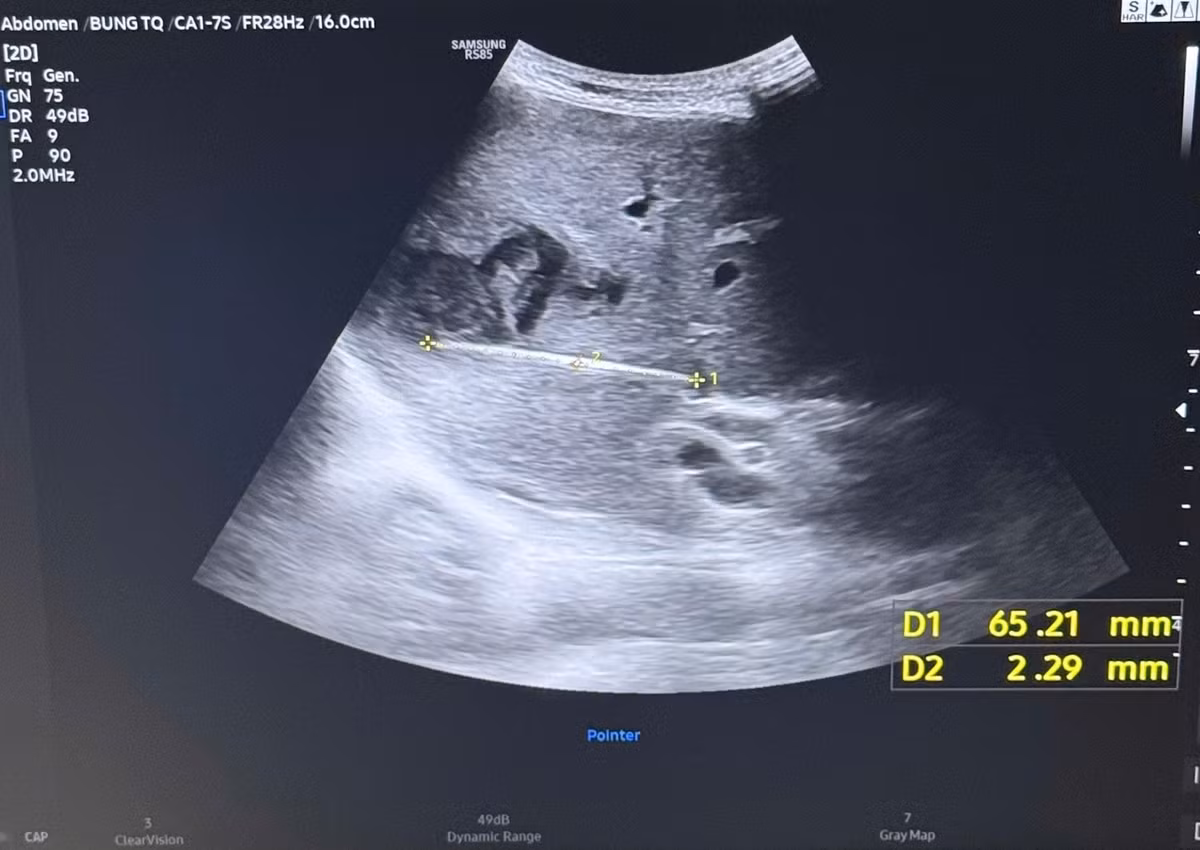

Bệnh nhân từng thăm khám và điều trị tại nhiều cơ sở y tế nhưng chưa xác định được nguyên nhân. Qua khám lâm sàng và tiến hành siêu âm bụng, các bác sĩ ghi nhận hình ảnh ổ áp xe gan, tuy nhiên, điểm bất thường là ổ áp xe nằm khá sâu, biểu hiện không điển hình. Vì vậy, bệnh nhân được chỉ định nhập viện để làm thêm các cận lâm sàng chuyên sâu.

Khi tiến hành siêu âm kỹ hơn, ê-kíp phát hiện một dị vật cản quang xuyên trong nhu mô gan, chiều dài ước tính khoảng 6-7cm. Ngay sau đó, bệnh nhân được chỉ định chụp cắt lớp vi tính (CT scan) ổ bụng.